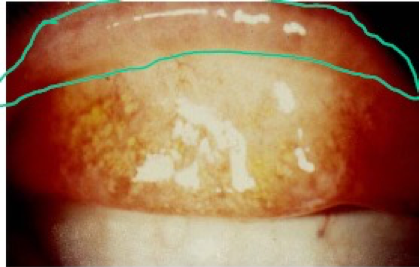

- TS (Trachomatous Scarring):

- Cicatricial changes of the upper eyelid conjunctiva

- Scarring of the upper eyelid conjunctiva

- Entropion (not part of grading but a key finding)

- Eyelid turns inward due to scarring

- ‘Rolled’ appearance of eyelid margin